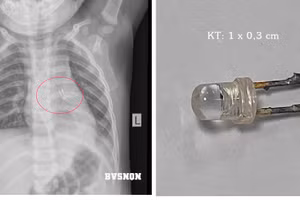

GD&TĐ - Bệnh viện E vừa tiếp nhận và cứu sống người bệnh nữ (67 tuổi, Hà Nội) bị thủng tạng rỗng do nuốt nhầm dị vật có chiều dài xấp xỉ 7cm.